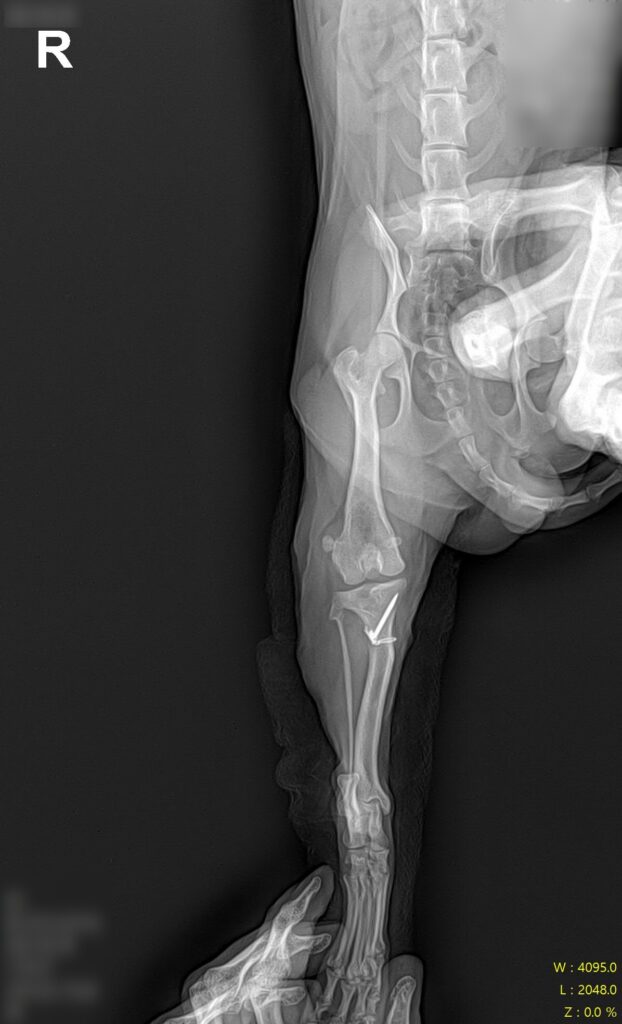

수술 후 방사선 사진 / 출처: 라온동물메디컬센터

수술 후에는 통증 관리와 함께 단계적인 재활 프로그램을 진행하며 체중 부하와 보행 회복 과정을 면밀히 모니터링하였습니다.

4기 슬개골탈구 교정을 위해 복합 술식을 진행하였습니다. 활차구를 깊게 다듬는 활차구 성형술, 틀어진 정렬 축을 바로잡는 경골 조면 이전술을 병행하였으며 변형 정도에 따라 뼈의 각도를 교정하는 처치도 함께 이루어졌습니다.